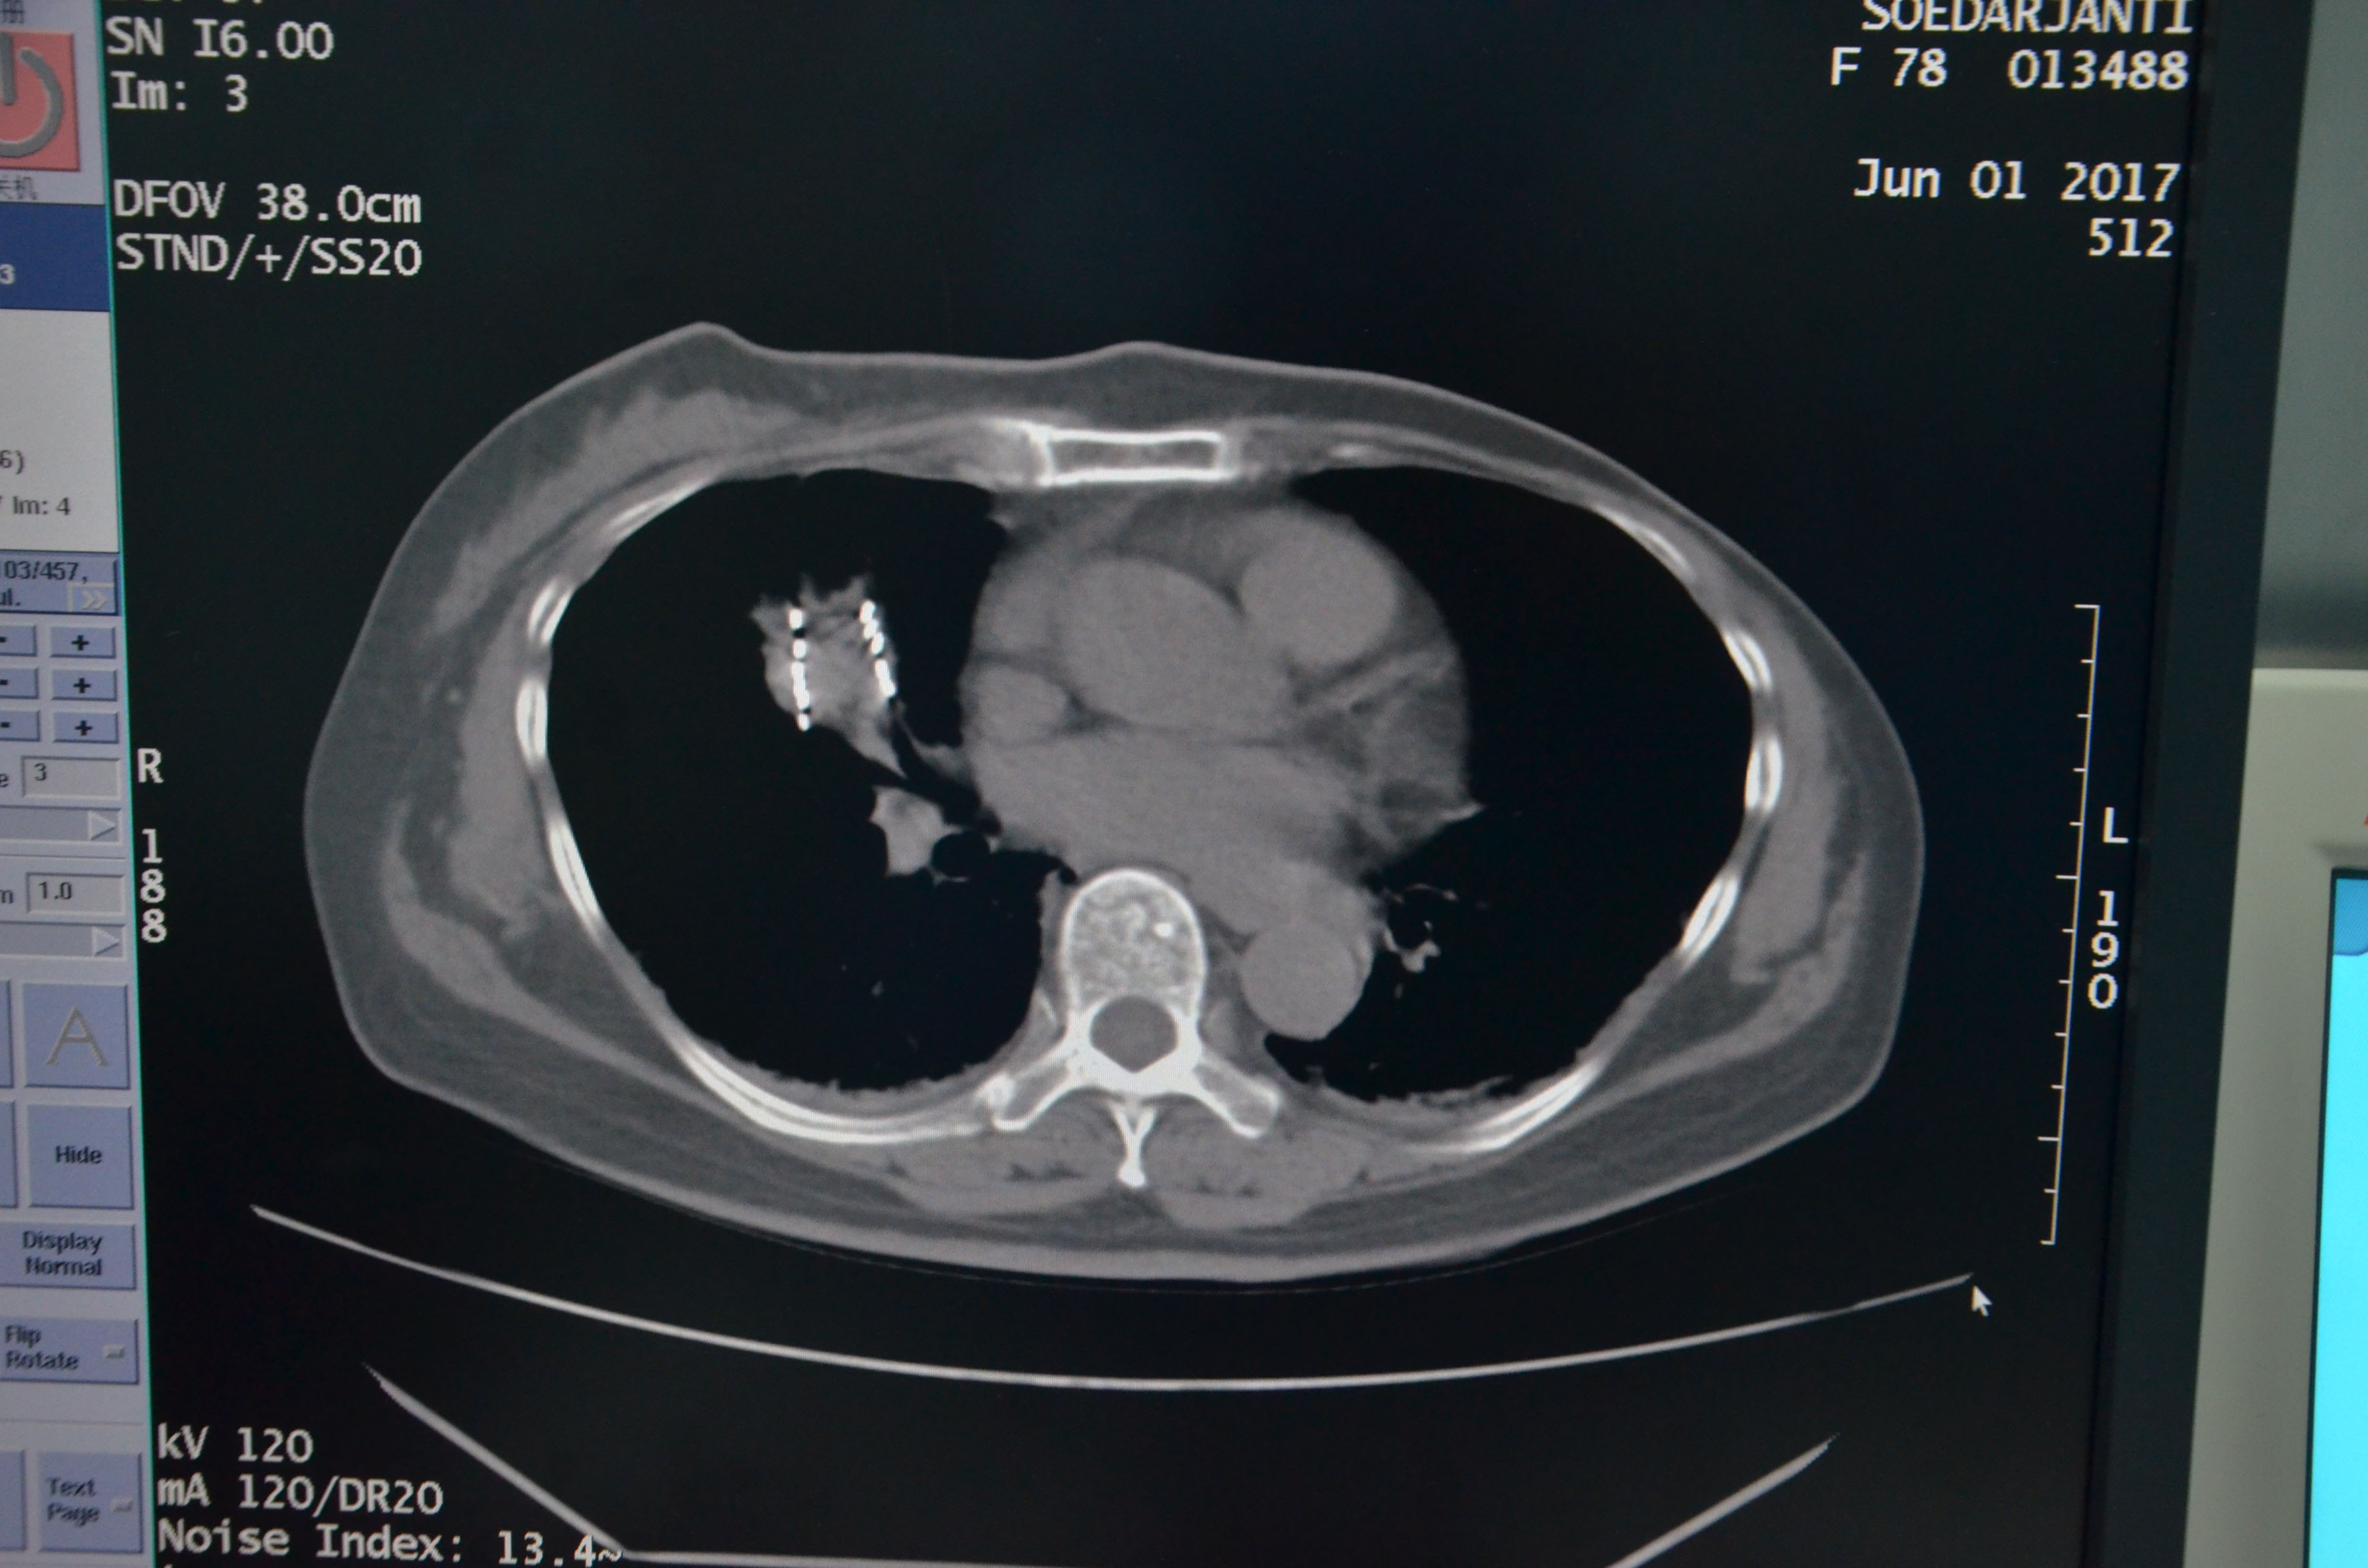

6月1日,醫(yī)院成功為該患者實(shí)施3D微創(chuàng)導(dǎo)向模板引導(dǎo)下的I 125粒子植入,術(shù)后患者身體狀況良好,病情控制穩(wěn)定。對粒子的分布作出劑量分析,完全符合術(shù)前的組織計劃劑量。

▲術(shù)后粒子分布,與術(shù)前組織計劃劑量吻合